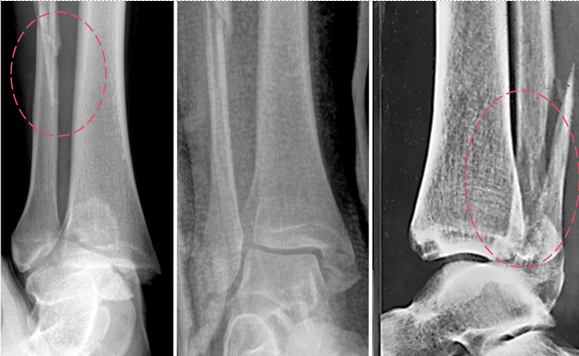

二、诊断要点:

X线:

AP位:胫腓重叠(tibiofibular overlap)

侧位:距骨后脱位、腓骨后移

CT(金标准):

确认腓骨移位

显示后踝骨折类型

发现隐匿性骨折(Tillaux、Wagstaffe)